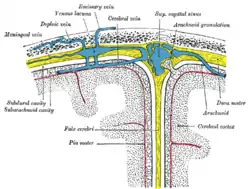

The inner surface of the skull-cap is concave and presents depressions for the convolutions of the cerebrum, together with numerous furrows for the lodgement of branches of the meningeal vessels. Along the middle line is a longitudinal groove, narrow in front, where it commences at the frontal crest, but broader behind; it lodges the superior sagittal sinus, and its margins afford attachment to the falx cerebri. On either side of it are several depressions for the arachnoid granulations, and at its back part, the openings of the parietal foramina when these are present.

Layers

Most bones of the calvaria consist of internal and external tables or layers of compact bone, separated by diploë. The diploë is cancellous bone containing red bone marrow during life, through which run canals formed by diploic veins. The diploë in a dried calvaria is not red because the protein was removed during preparation of the cranium. The internal table of bone is thinner than the external table, and in some areas there is only a thin plate of compact bone with no diploë.[2] Calvarial bones are supplied by endosteal and periosteal sheaths which are innervated by the nociceptors, sensory, sympathetic, and parasympathetic nerves. Horizontal section of the mouse pups showed that the density of nerve fibers was highest in the region of forehead, temples, and the back of head which crossing the frontal, parietal, and interparietal bones. In the calvarial innervation in the adult mouse, CGRP-labeled fibers and peripherin were seen in the sutures, emissary canals, and bone marrow but not in diploe. Nerve fibers passing through the emissary canals and cavity of bone marrow provided the branches of periosteal and dural nerves whereas fibers from the sutures gave out to the dural nerves.[3]